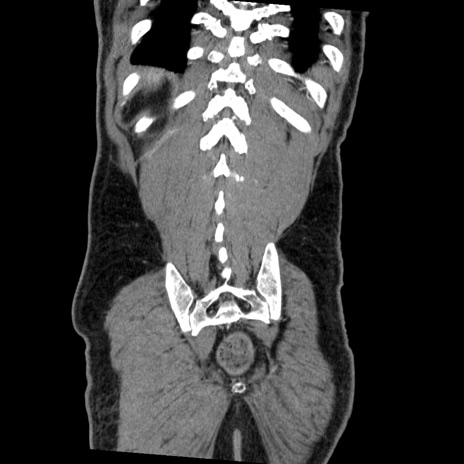

症例22(冠状断像)

【症例】50歳代男性

【主訴】腹痛

【現病歴】AVMからの被殻出血のため回復期リハ病棟入院中。 本日午後3時頃急に下腹部痛が出現した。

【既往歴】AVM、被殻出血、虫垂炎、高血圧

【身体所見】意識晴明、左半身不全麻痺、会話の理解は良好、36.5°C、腹部:膨隆、全体に板状硬、下腹部正中に圧痛点あり、反跳痛-、筋性防御不明、右下腹部にope scar

【データ】WBC 9400、CRP 0.06